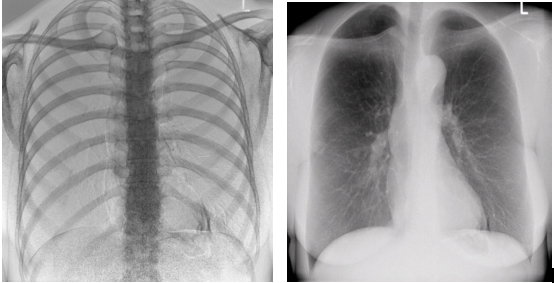

普利德的动态大平板DR http://www.pl999.com/class.php?anclss=1&nclass=406超清影像系统,可发现早期小斑片影和间质改变,也可发现肺部磨玻璃影、浸润影等,能够辅助医生对疑似病例进行准确诊断。

动态大平板DR一机多用,即能拍摄早期小斑片影和间质改变,也可发现肺部磨玻璃影、浸润影等。>28帧/s的超清图像,0.7秒动静功能切换,满足大量新冠肺炎胸部诊断需求,专为发热门诊等疾控机构量身定制。想了解具体参数及价格信息等,欢迎留言或致电400-6656-888